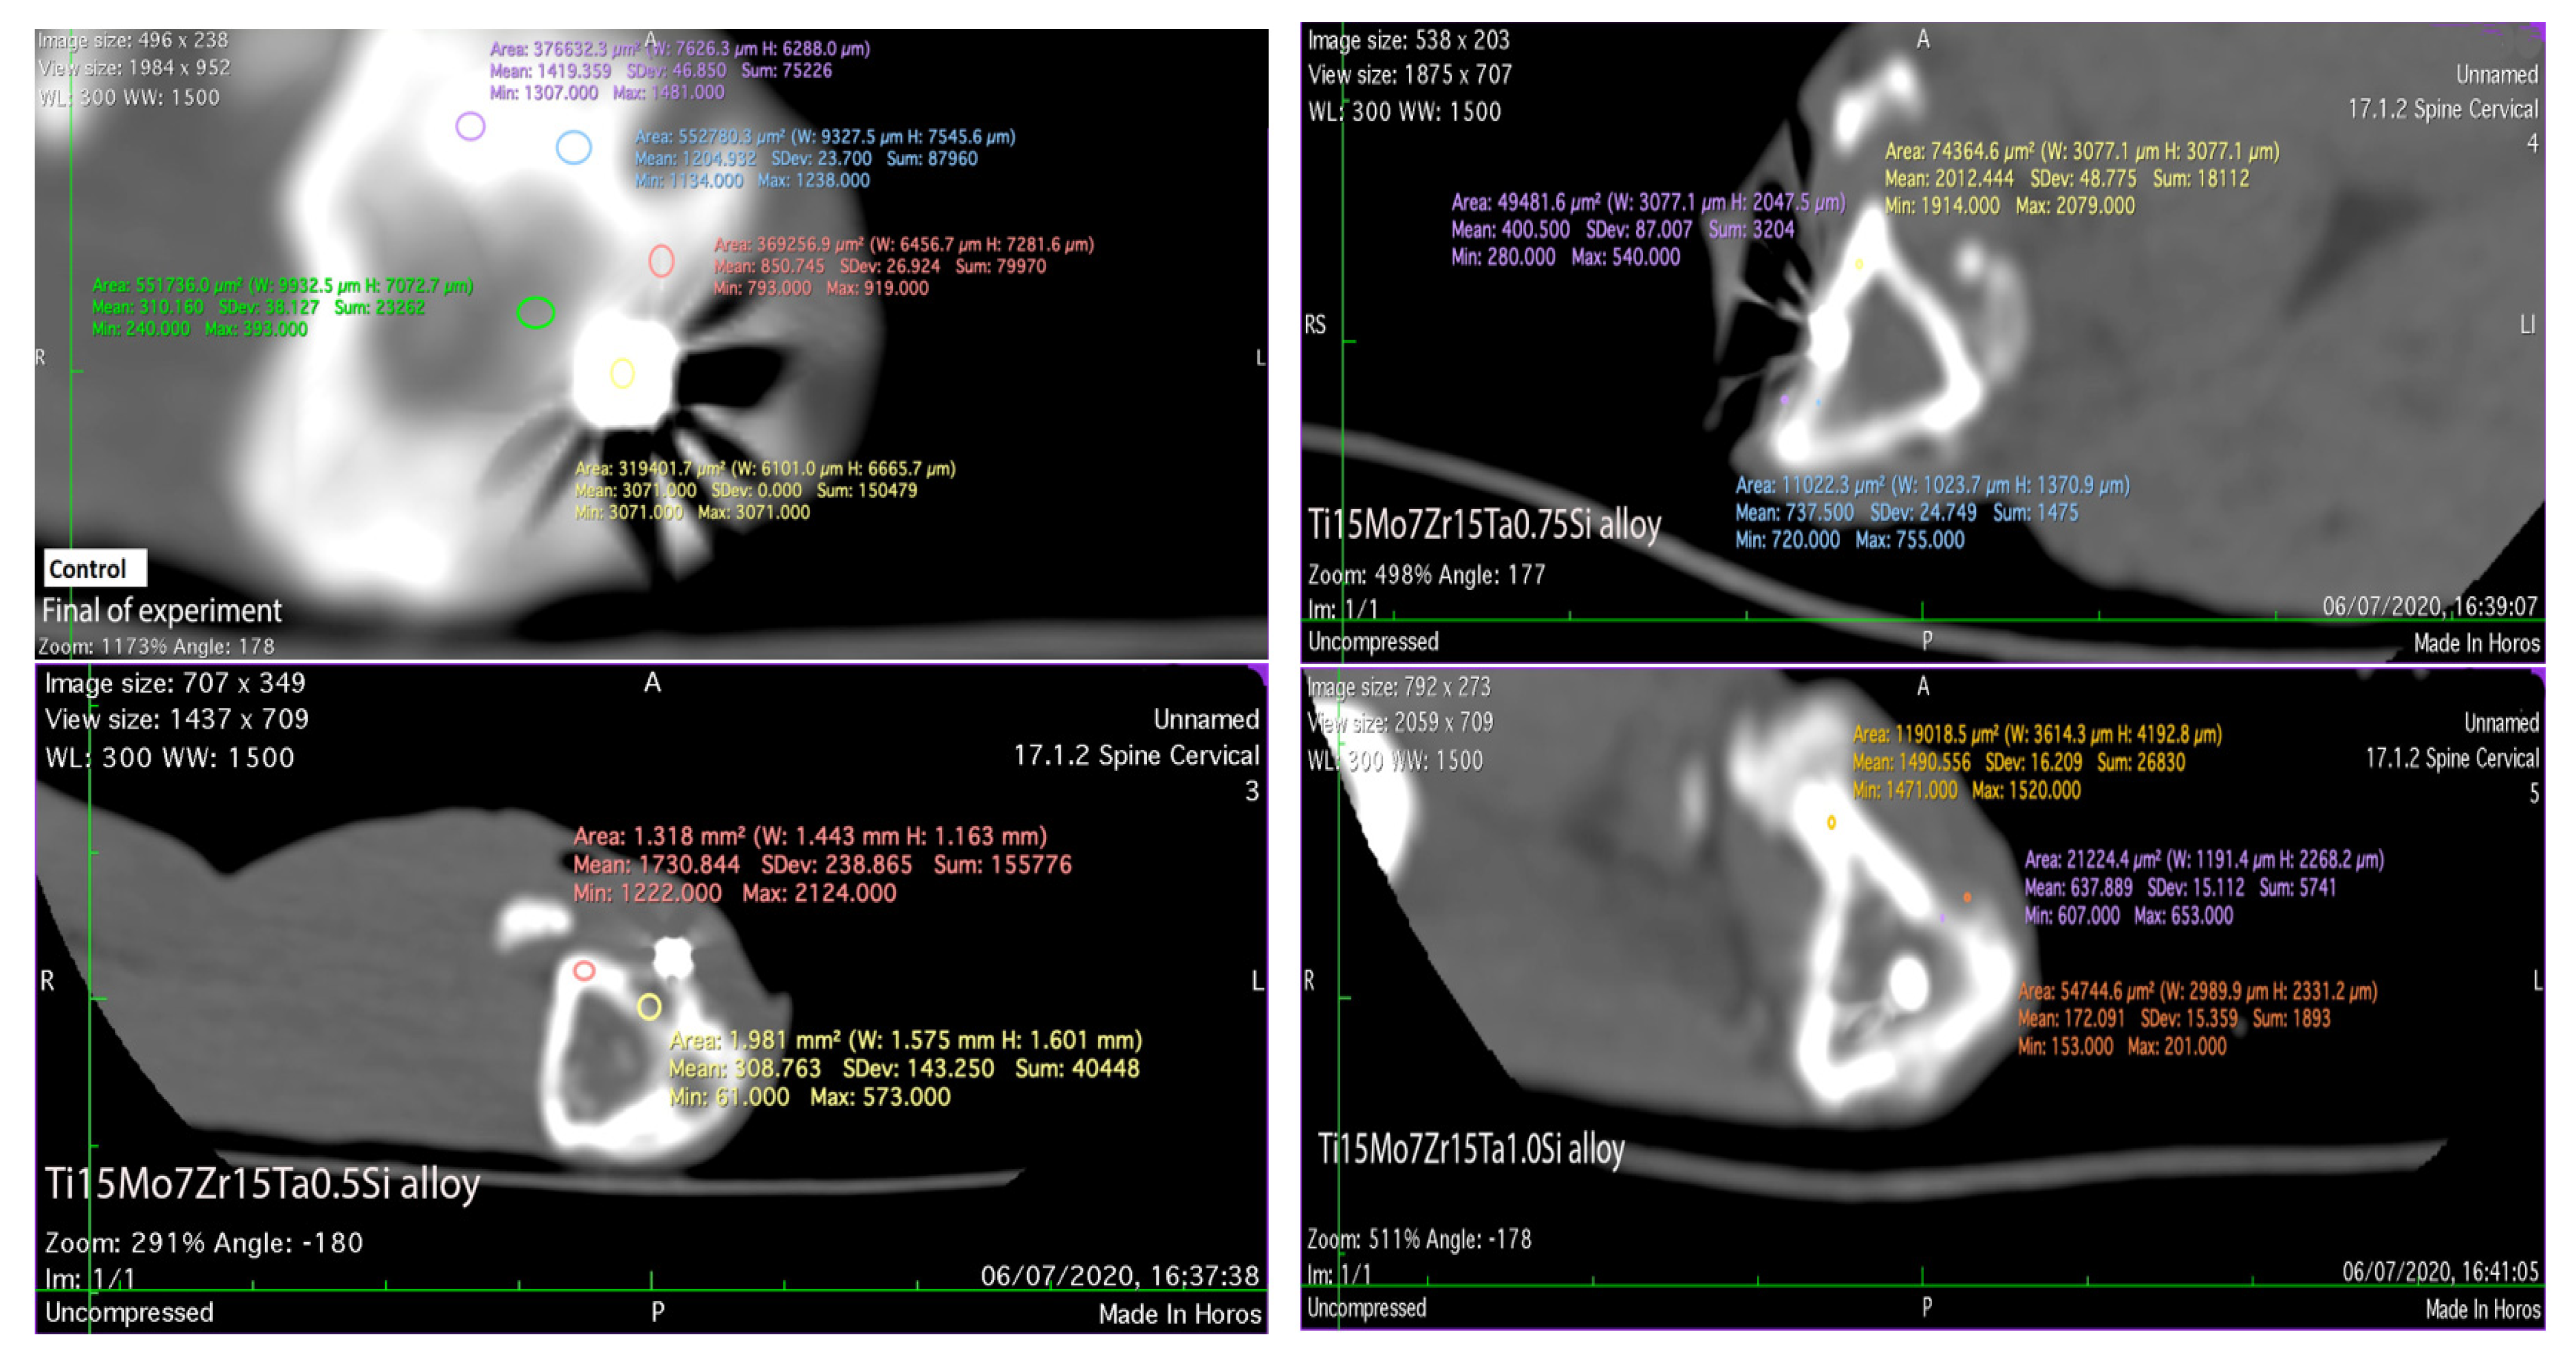

Because each individual has a slightly different bone density, even if they are females and similar in ages and weight, the bone radiodensity highlighted by CT scan and measured in UH slightly varies, falling within the physiological average of 1125 UH [36,37]. In the CT scan, the Hounsfield unit shows some values which are in direct relation to the degree of X-ray attenuation that is allocated to each pixel, finally obtaining the images which express the density of each tissue [38,39].

Regarding the radiodensity of the implant surrounding tissues, after 60 days of experiments, in the control rabbit, the newly formed tissue in the implantation gap measures 793 UH, which is determined by the placing of the iron rod into the bone marrow duct. In the case of TI15Mo7Ta15 the new bone counted a density of up to 698 UH (and its bone compacta between 1359 and 2127 UH), and about 633 UH (the tibial compacta about 1520 UH) in the case of the alloy Ti15Mo7Zr15Ta1.0Si. Lesser radiopaque tissue of up to 573 UH (at tibial compacta between 1222 and 2124 UH) was registered in the case of the Ti15Mo7Zr15Ta0.5Si alloy and the higher radio-opacity of approximately 755 UH (bone compact of about 2079 UH) in Ti15Mo7Zn15Ta0.75Si (Figure 8). The radio-opacity identified in the newly formed tissue around the implants is associated with the fibrous tissues with cartilage islands and ossification punctures formed during the bone remodeling and implants osseointegration, which is confirmed by histologic analyses [11,12,40].

Figure 8.

CT scan of the implanted area in control and experimental rabbits after 60 days.